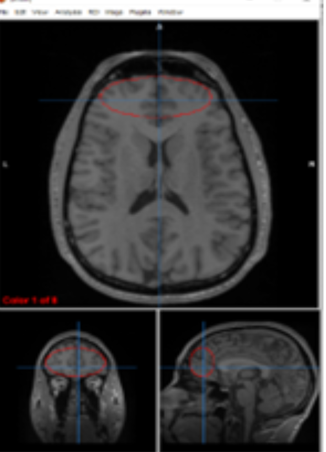

insular cortex

emotion

prefrontal cortex

judgement, inhibition,and decision making

primary somatosensory cortex

perception/ touch

primary motor cortex

initiating and executing voluntary movements

white matter

communication